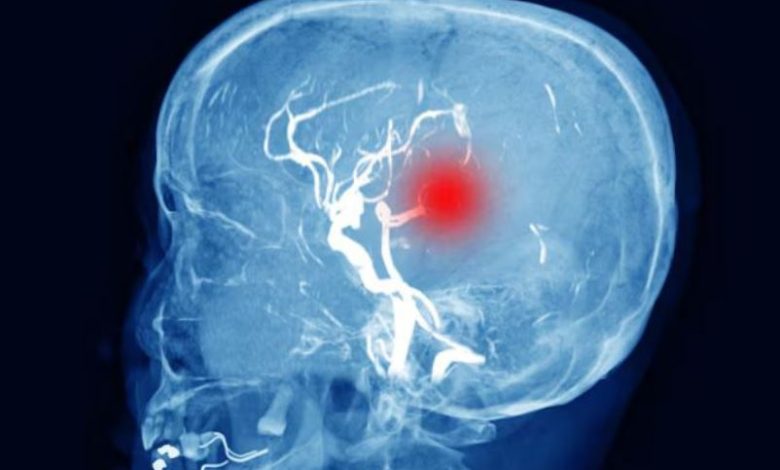

बीएचयू के न्यूरो सर्जरी विभाग में ब्रेन इंजरी के बाद मरीज की सीटी स्कैन रिपोर्ट। इसमें दिमाग में भरा पानी (काले रंग में) देखा जा सकता है।